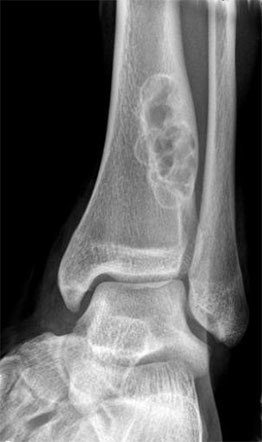

Bone tumors are rare lesions. A large part of these tumors are benign lesions, and they often occur by chance during radiological examinations for another reason. As a complaint, they usually show swelling and pain. Rarely, it is diagnosed after causing a fracture in the place where it was. Osteoid osteoma, osteochondroma (exostosis), enchondroma, non-ossifying fibroma, eosinophilic granuloma, simple bone cyst, fibrous dysplasia and intraosseous lipoma/ganglion are the most common lesions of benign tumors.